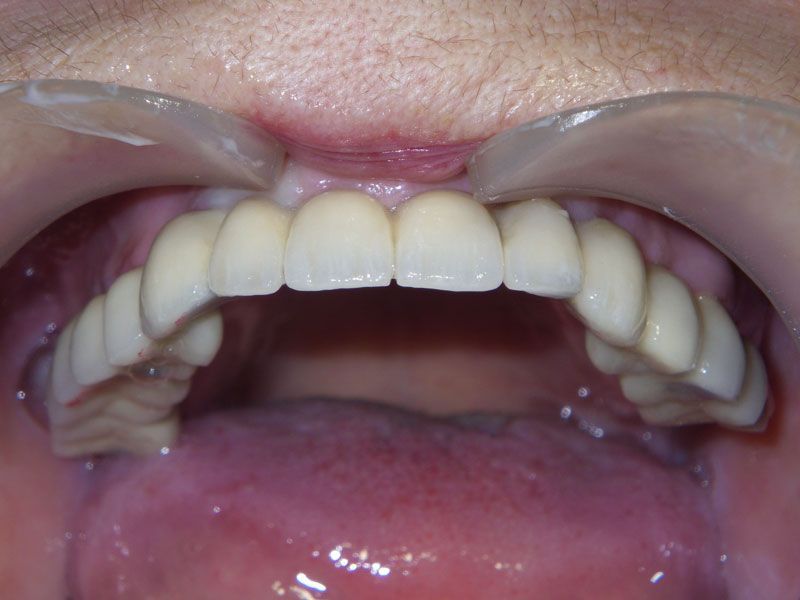

Протезирование было проведено с помощью трех мостовидных протезов, причем выбор цвета и формы зубов был предоставлен пациенту. Оказалось, что высоко-эстетичнын зубы, были мечтой пациентки всю жизнь. Они и были выбраны. Диссонанс с собственными зубами, которыми так дорожила наша пациентка до операции, оказался столь сильным, что теперь в планах пациентки заняться нижней челюстью в плане функционально-эстетическойй реабилитации фронтального участка несъемным протезированием на имплантах.